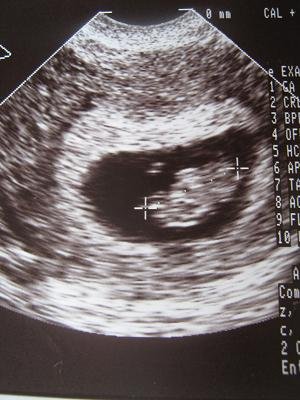

18mm, szépen fejlődik és dobog továbbra is. Viszont amellett, hogy az alkohol és a bagó volt az első dolog, amit ezen a világon megkívánt, közveszélyes munkakerülő is lesz, mert miatta nem mehetek vissza dolgozni. Ó milyen szörnyű csapása ez a sorsnak!!! (kegyetlen vigyor)